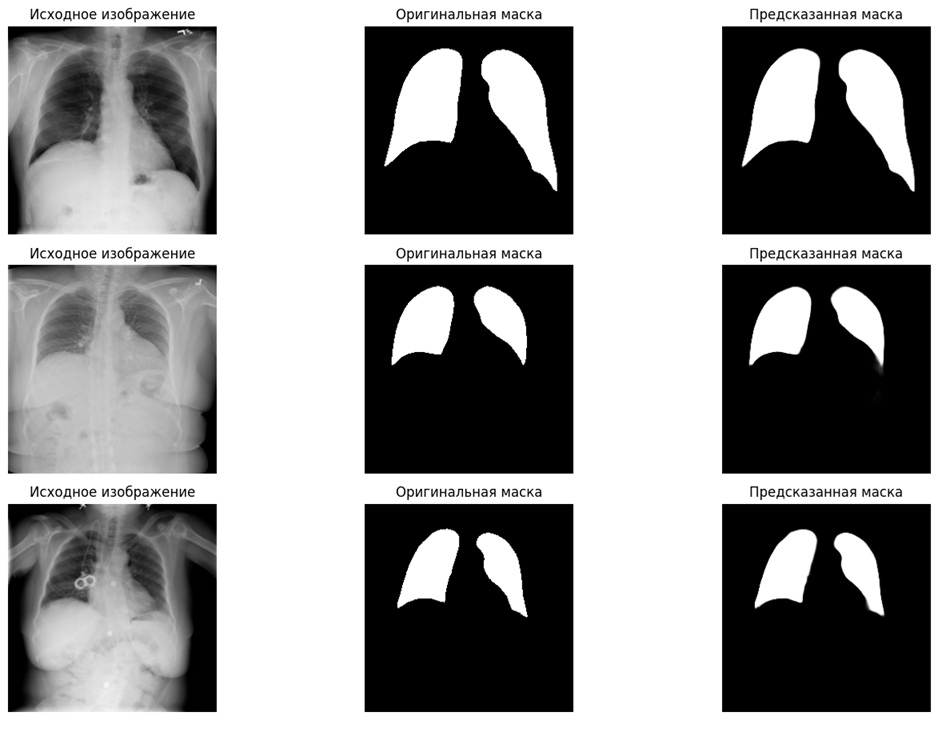

📊Визуализированы результаты, позволяющие сравнить оригинальные снимки, маски и предсказания модели

✅Система стабильно распознаёт границы лёгких даже на сложных снимках

✅Достигается высокая точность сегментации, близкая к экспертной разметке

✅Возможна наглядная проверка качества работы через визуализацию результатов